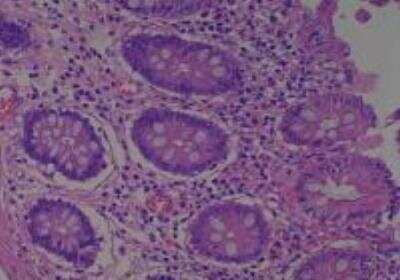

Scientific Data Images for Human Multi Tissue MicroArray (Normal Adjacent)

Hematoxylin & Eosin Stain: Human Common Tissue MicroArray (Normal Adjacent) [NBP2-30215] - 103. Stomach